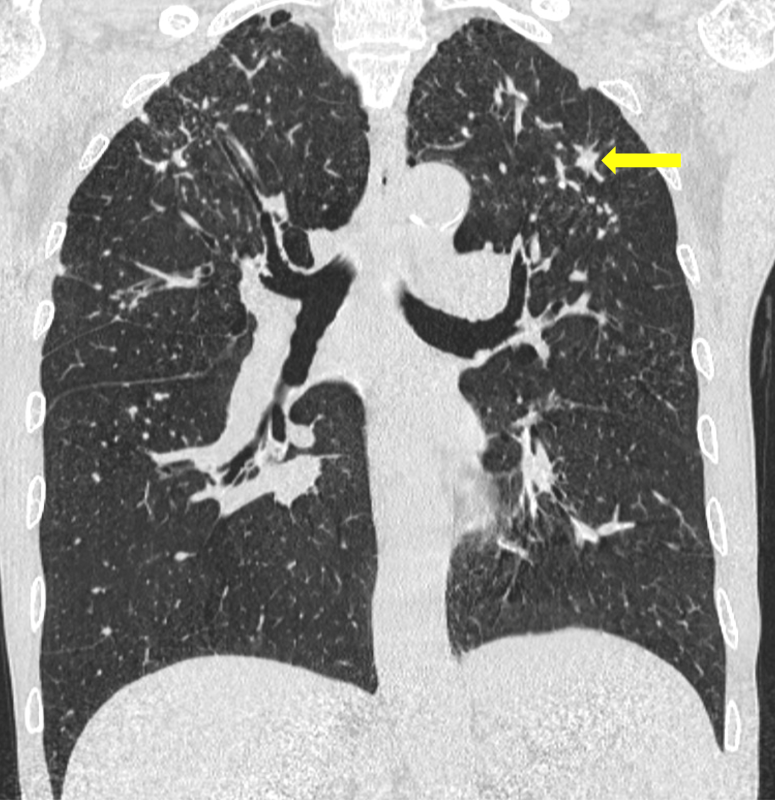

肺结节病影像

双肺弥漫粟粒状结节影请各位大神分析